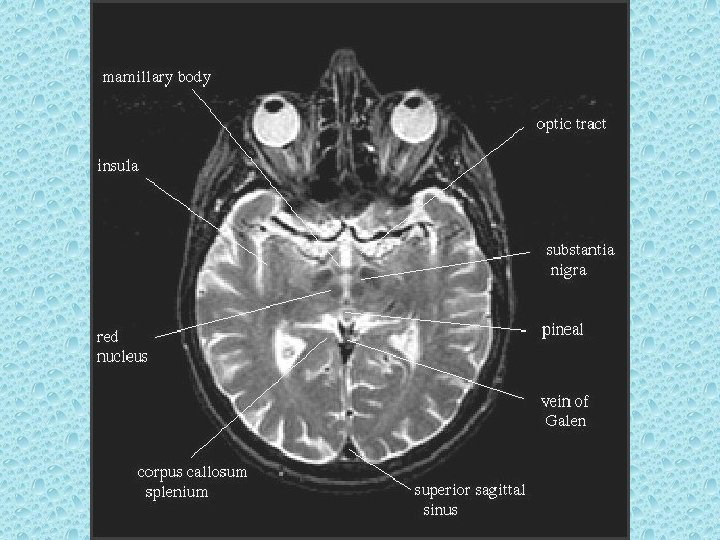

SEREBRAL PARANKİMDE BULUNAN YAPILAR • • Beyaz ve gri cevher Girus ve sulkuslar Lentiform nükleus: Putamen ve globus pallidus İnternal ve eksternal kapsül Talamus Kaudat nükleus ve korpus kallozum Ventriküller Koroid pleksus

VENTRİKÜLLER • Lateral ventriküller: frontal, oksipital ve temporal hornlar, korpus ve atrium • Foramen monro • 3. Ventrikül • Akuaduktus silvii • 4. Ventrikül • Foramen Lucka (çift) ve magendi (tek)

SEREBRAL VENLER • • • Süperior sagittal sinüs İnferior sagital sinüs Konfluens sinüs Strait sinüs (düz veya sinüs rektus) Galen veni Kavernöz sinüs Transvers sinüsler Sigmoid sinüsler İnternal juguler venler